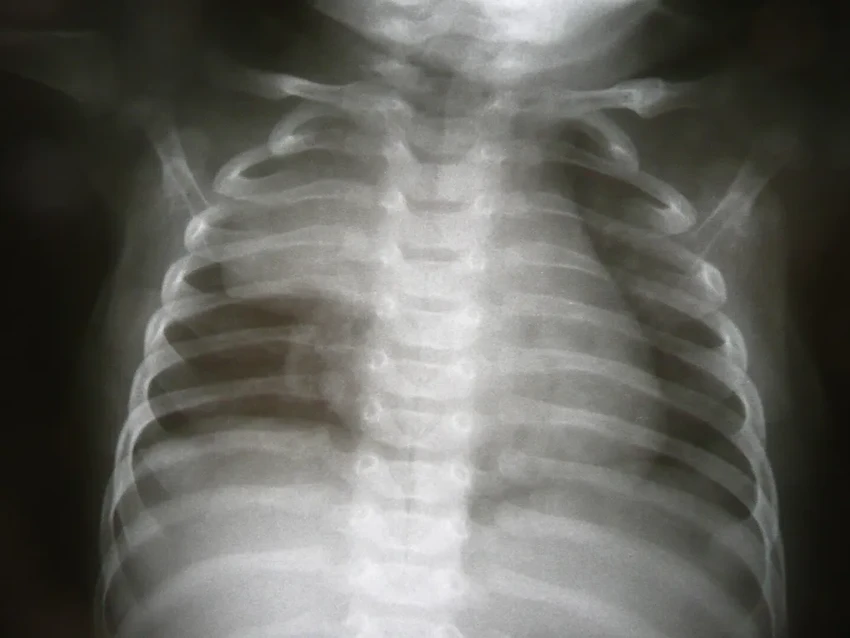

Всем известно, что в детстве тимус — настоящая «школа» для иммунитета. Именно здесь созревают Т-лимфоциты — те самые клетки-защитники, которые борются с инфекциями и болезнями. Если железу удалить в молодом возрасте, количество и разнообразие этих клеток остаётся сниженным на всю жизнь.

- Дети без тимуса даже хуже реагируют на прививки — их иммунная система просто не может правильно «запомнить» врага. Считалось, что к половозрелому возрасту железа «выполняет свою миссию», сморщивается и становится почти бесполезной. Её даже начали иногда удалять «заодно» во время операций на сердце — она ведь мешает хирургу, верно? Но так ли это на самом деле?

Исследователи из Бостона проанализировали данные тысяч пациентов, перенёсших операции на грудной клетке. Они сравнили две группы: тех, кому тимус удалили (1146 человек), и тех, кому его оставили (более 6000 человек). Результаты поражают.